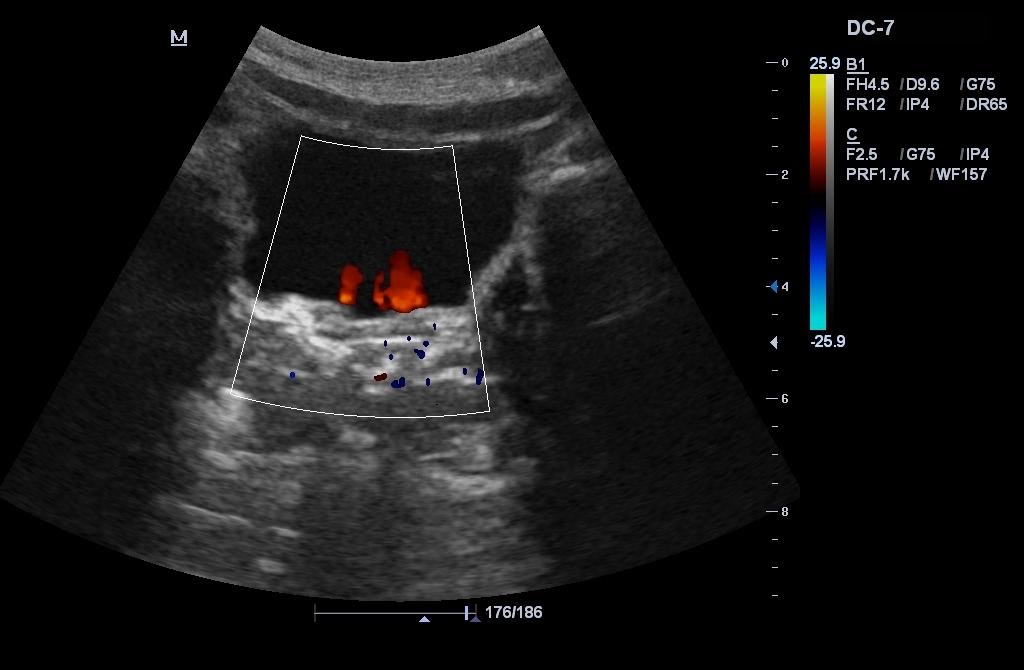

Области применения: абдоминальные исследования, акушерство и гинекология, кардиология, ангиология, нефрология, урология, онкология, педиатрия, неонатология, исследования поверхностных органов и костно-мышечной системы, молочной железы, транскраниальная эхография.

Опция QuickScan автоматически оптимизирует изображение и настройки шкалы импульсно-волнового допплера

Опция FSI (Full Spectrum Imaging) - улучшает B- изображения за счет создания более широкого спектра ультразвуковой волны

PIH (пульс-инверсная гармоника) - делает визуализацию четкой за счет контрастности и ясных границ

PPIHI (Power Pulse Inversion Harmonic Imaging) – энергетическая пульс-инверсная гармоника. Технология выделения гармонической составляющей колебаний внутренних органов, вызванных прохождением сквозь тело базового и инверсного ультразвуковых импульсов. Делает изображение четче, потому что оба сигнала (базовый и инверсный) проходят сквозь тело и при сложении автоматически подавляются шумы